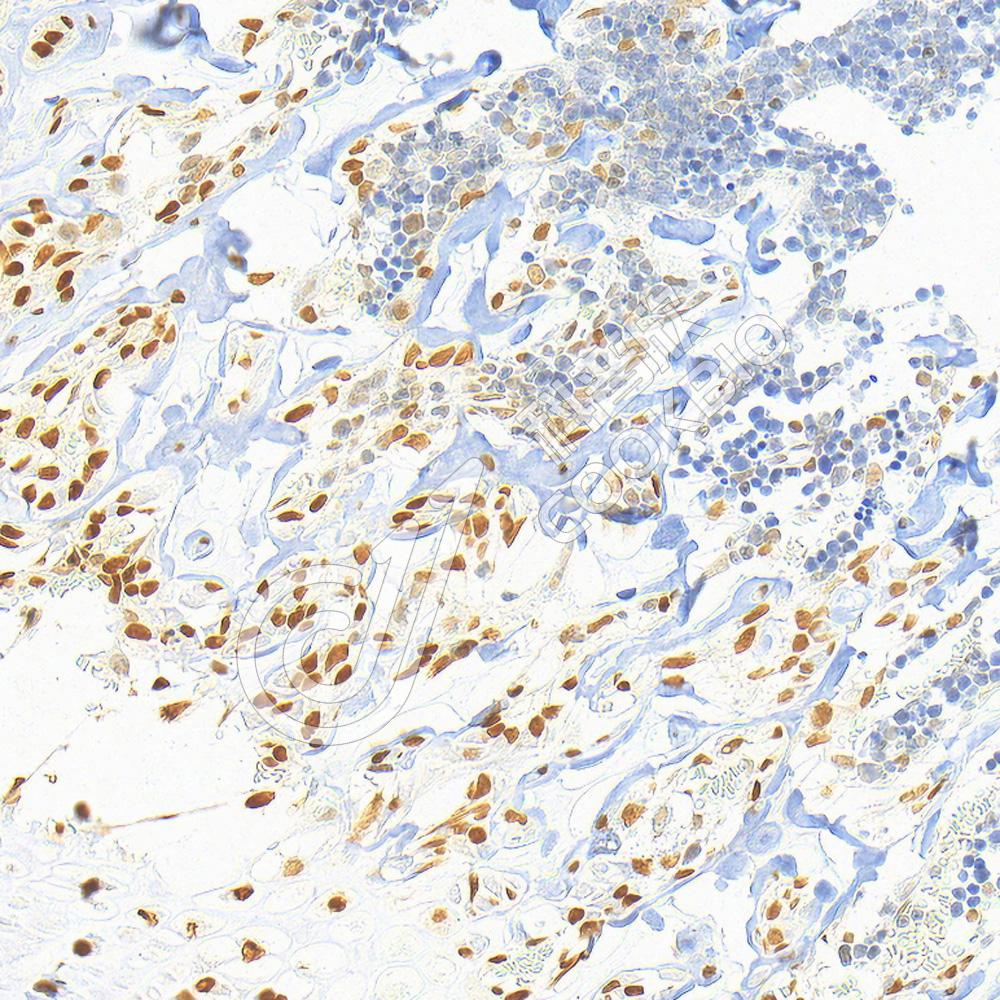

IHC检测RUNX2蛋白(货号 K2376893).

样品: 人扁桃体, 4%多聚甲醛 (货号KSG1101) 固定12-24小时.

抗原修复: 柠檬酸抗原修复液(干粉, pH 6.0) (KSG1201), 高压锅均匀喷气计时2分钟.

—抗: 1: 1000稀释, 4℃ 孵育过夜.

二抗: S-vision免疫组化多聚二抗(山羊抗小鼠), 即用型(货号KB3903), 室温孵育20分钟.